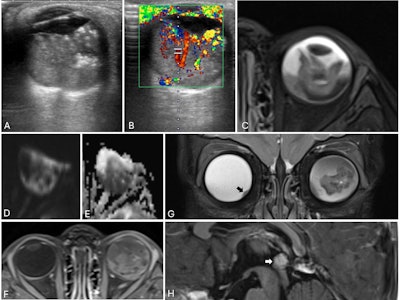

Trilateral retinoblastoma in a 21-month-old child. (A) Axial ultrasound of the left eye shows a solid, heterogeneous mass adherent to the posterior globe wall with echogenic foci suggestive of calcifications. (B) Color Doppler confirms internal vascularity. (C) Axial T2-weighted MRI demonstrates a heterogeneously hypoechoic intraocular lesion with a fluid level. (D-E) The mass is hyperintense on diffusion-weighted imaging and hypointense on the apparent diffusion coefficient (ADC) map, consistent with restricted diffusion. (F) Post-contrast images show heterogeneous enhancement. (G) Coronal T2-weighted image reveals a small nodular soft-tissue elevation in the inferomedial right globe (black arrow), indicating bilateral disease. (H) Sagittal post-contrast T1-weighted image demonstrates an enhancing pineal lesion with associated restricted diffusion (not shown), suggestive of a pineoblastoma, consistent with trilateral retinoblastoma.